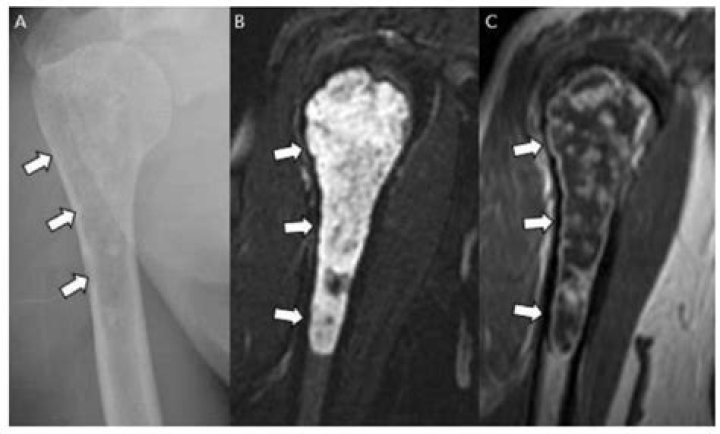

Malignant transformation is seen in 1% of solitary osteochondromas and in 3%–5% of patients with HME. Continued lesion growth and a hyaline cartilage cap greater than 1.5 cm in thickness, after skeletal maturity, suggest malignant transformation.